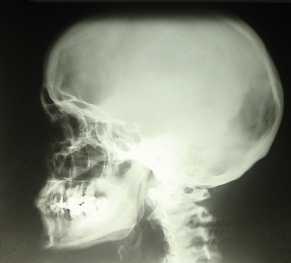

На дому врач соберет подробный анамнез и проведет осмотр пациента, подберет схему лечения и даст исчерпывающие рекомендации по лечению и дальнейшей профилактике. На дому также возможен забор анализов для лабораторных исследований. При необходимости, на весь период лечения оформляются больничные листы, выписываются рецепты. По показаниям наш врач-невролог назначит консультации смежных специалистов, дополнительные обследования (рентген, УЗИ, дуплексное сканирование, холтеровское мониторирование, велоэргометрию, диагностику функций внешнего дыхания, ЭЭГ и т.д.) или эфферентные методы лечения, которые Вы сможете пройти амбулаторно в нашей клинике или в условиях нашего комфортабельного дневного стационара.